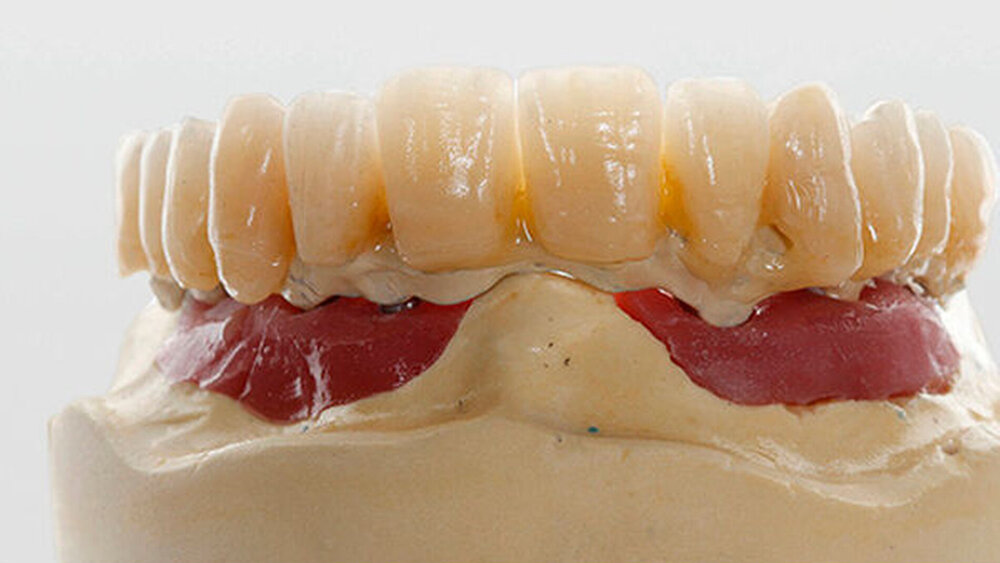

Bei Interimsversorgungen bis zur Osseointegration und der sich anschließenden prothetischen Phase (etwa drei bis vier Monate). Werden die inserierten und freigelegten Implantate mit einem Langzeitprovisorium versorgt, bleibt dieses bis zur Adaptation sechs bis acht Monate in situ. Bis der All-on-four-Patient sein verschraubtes Provisorium richtig adaptiert hat, vergehen auch fünf bis sechs Monate. Die Dauer des Provisoriumtragens unterscheidet sich also nicht wesentlich.

Eine 67 Jahre alte Patientin stellte sich mit dem Wunsch einer Oberkiefersanierung in unserer Praxis vor. Ihre Restzähne waren aufgrund von Parodontitis und funktioneller Überlastung nicht mehr erhaltungswürdig. Wir ließen sie bis kurz vor der definitiven Versorgung als strategische Pfeilerzähne für die Interimsprothese in situ.

Nein, aber das ist möglich. ZTM Stefan Picha hat die prothetische Versorgung übernommen.